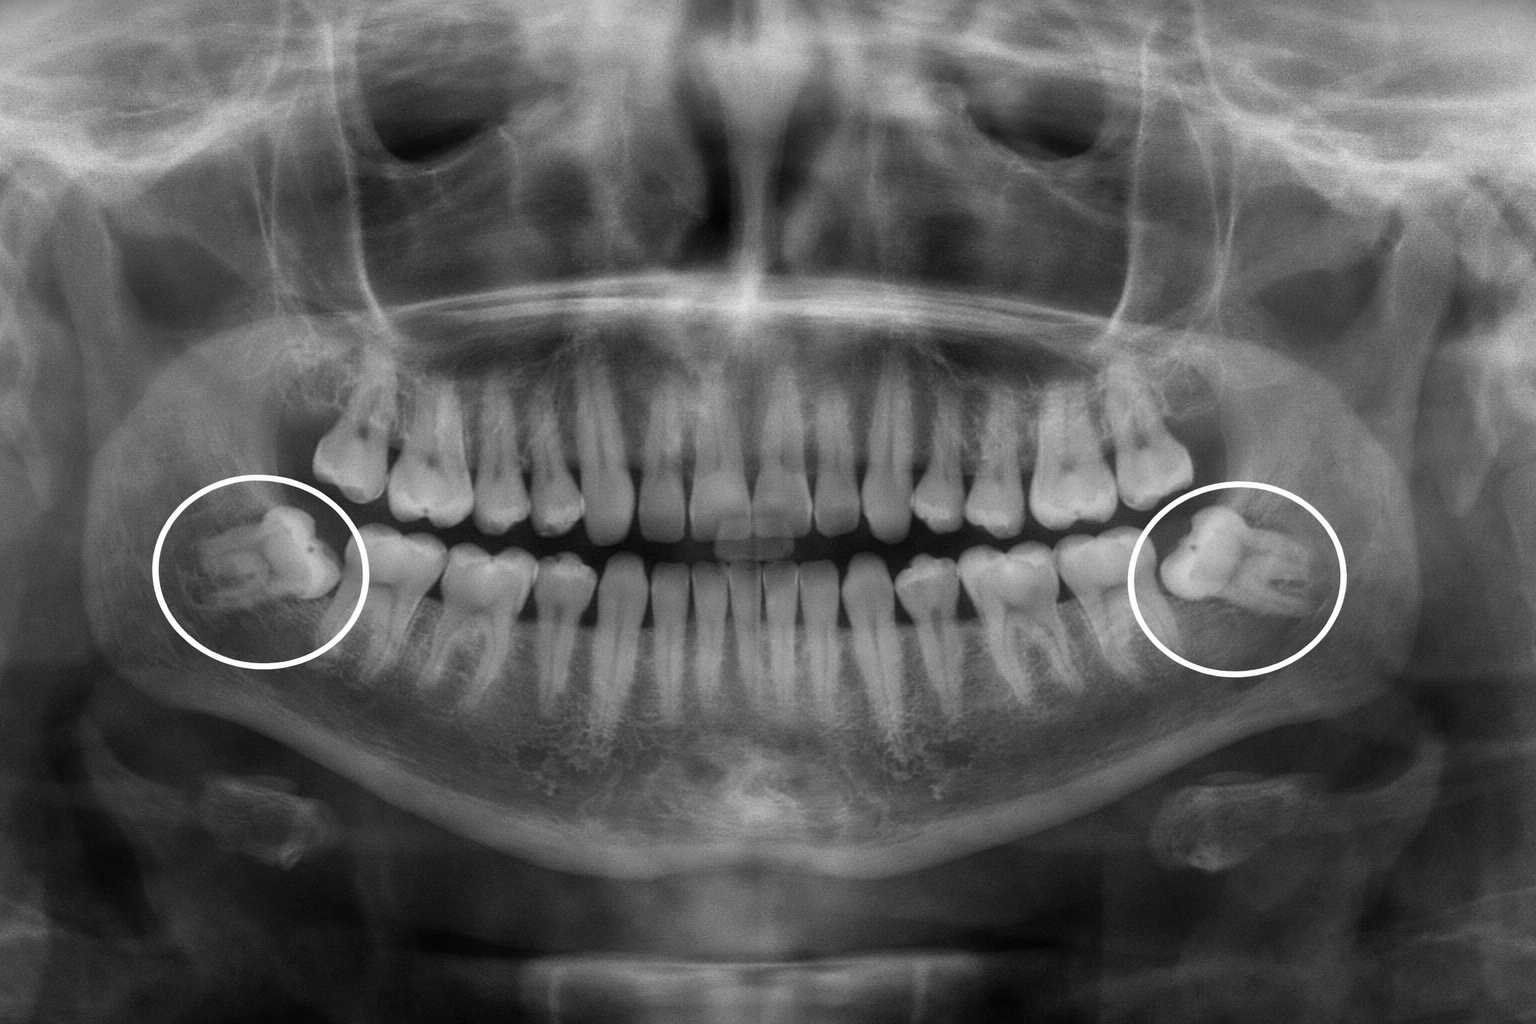

Wisdom teeth can cause pain, infections, swelling, and dental misalignment if not treated on time. Dr. Esteban Ramírez performs wisdom teeth extraction using precise techniques designed to minimize discomfort and support a smooth recovery.

Wisdom Teeth Extraction Illustration

• Safe removal of impacted wisdom teeth